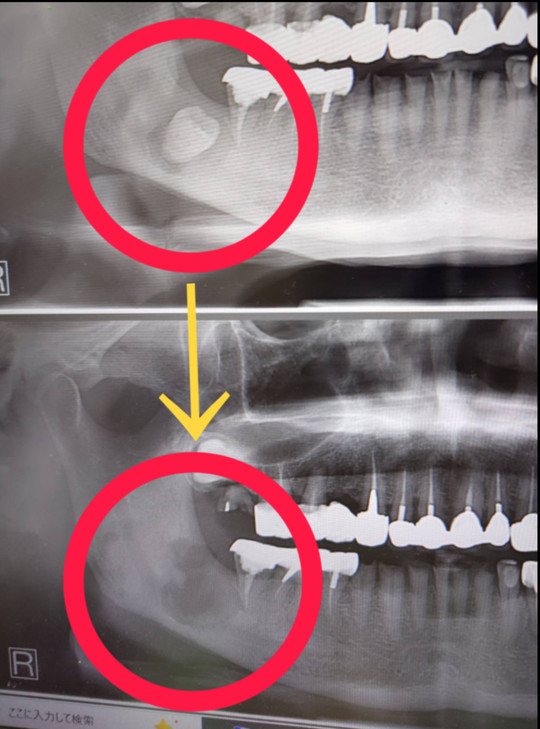

教育用のデンタルモデル、上下の歯列が詳細に再現されています。デンタルスチーマー ロコモ LOCOMO 歯科 ほぼ未使用。.:*・゜新品未使用☆。歯科インプラント補綴用器具 新品未使用。NISSIN 口腔外科用顎模型 P15-OOP.1 定価は税込36300円です。名前が書いてあるので、神経質な方はお控え下さい。☆。.:*・゜ ReFa リファ クリア。#歯科#口腔外科#実習